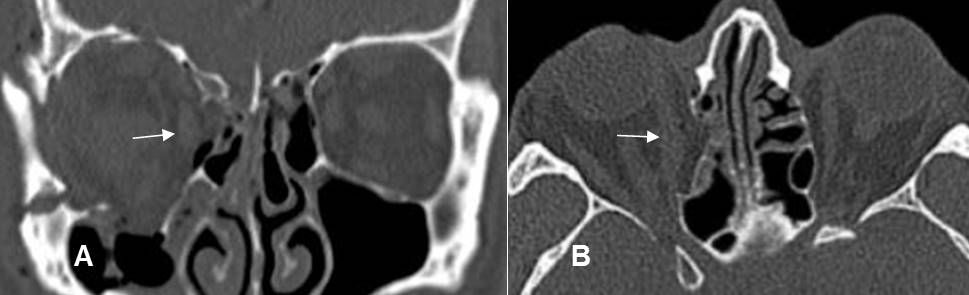

Fig 218 A. Fractura de órbita.

TAC reconstrucción coronal. Estallido facial con múltiples fracturas y compromiso del borde interno de la órbita derecha. Los rectos interno e inferior están desplazados y redondeados por edema, pero no atrapados.

Fig 218 B. Fractura de órbita.

TAC axial. Fractura en el borde medial de la órbita con edema del músculo recto interno. Está desplazado medialmente y se debe sospechar su atrapamiento. (Flecha delgada). Adicionalmente hay cambios inflamatorios en el espacio intraconal e irregularidad del nervio óptico. (Flecha gruesa).